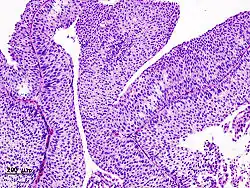

Urothelkarzinom der Harnblase

Lichtmikroskopisches Präparat, gefärbt mit HE